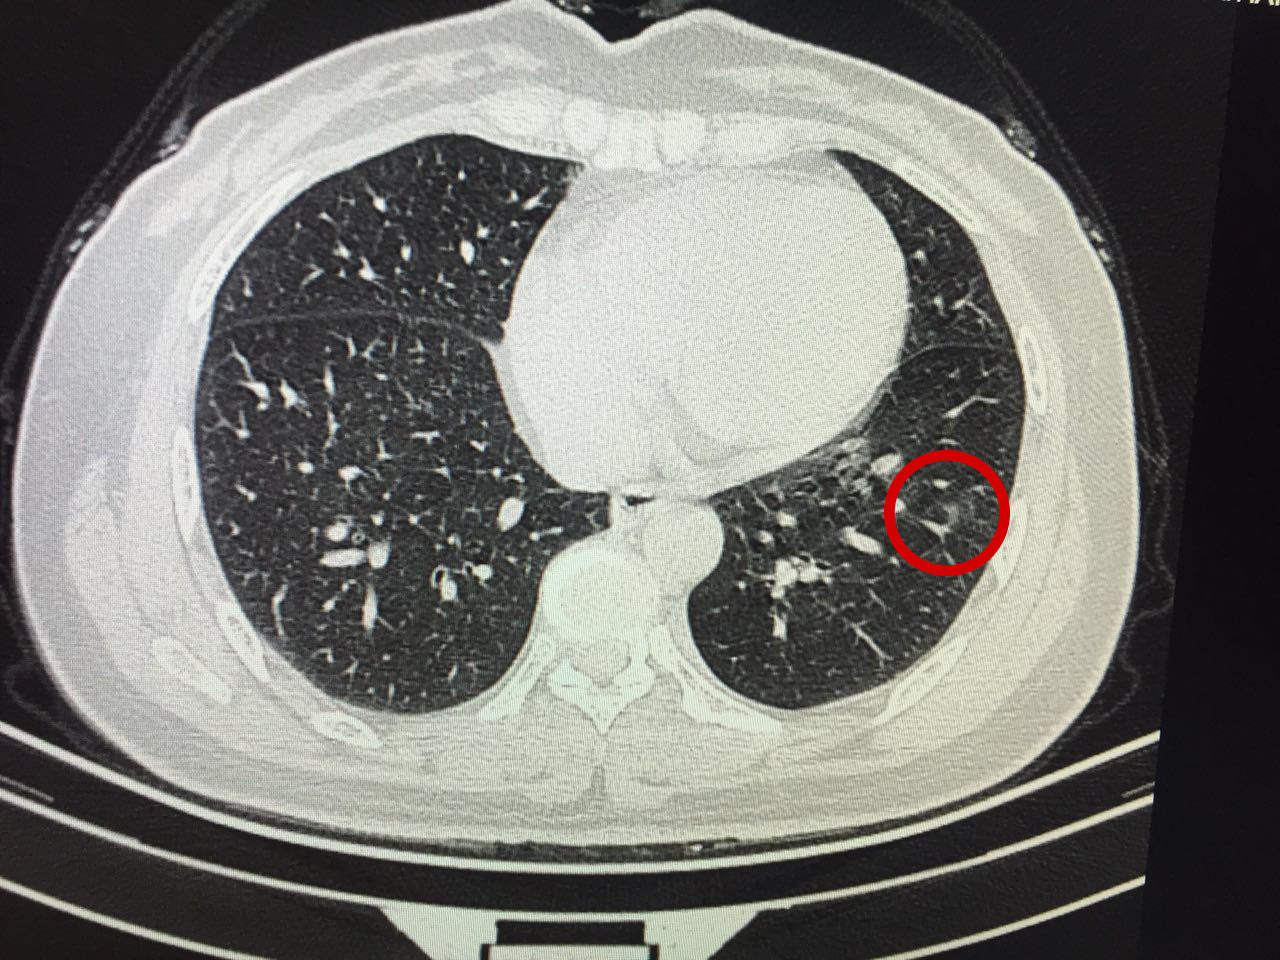

一个月后,吴女士再次来到肺结节中心进行第二次复查,而结果简直令她惊喜——结节已缩小至6mm,几乎都看不清了!

“挺好的!之后三个月到半年来随访一次就行了,危险性不大。”看到最新的结果,王剑飞也忍不住眉开眼笑。